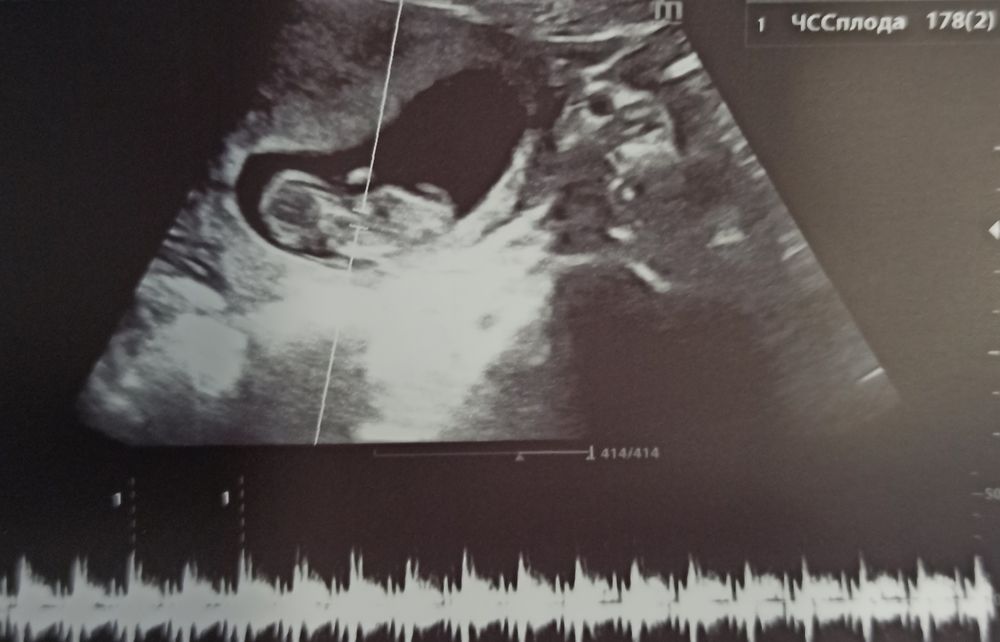

УЗИ 65 дпо (11+1) ❤🤞🤞🤞

Я стала переживать по поводу тахикардии плода, но я буду верить и надеяться, что ЧСС замедлится до нормы до 160 уд/мин, а как сейчас 170-180 уд/мин - это многовато на этом сроке (12 неделя), так частить сердечко может в норме до 9 недель, а далее должно замедляться постепенно. Домашним допплером пишет также до 170-178 уд/мин. Через неделю схожу снова на УЗИ, а потом, 2 мая будет 1 скрининг. Вот нашла табличку норм, не сильно, но превышает: